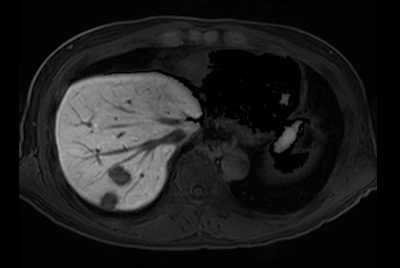

Liver hemangioma with Compressed SENSE